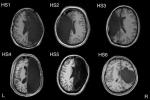

В 2019 году группа исследователей из Калифорнийского технологического института проанализировала мозг шести взрослых людей в возрасте от 20 до 30 лет, перенесших гемисферэктомию — редкую нейрохирургическую операцию по удалению половины головного мозга. Эта процедура показана в экстремальных случаях эпилепсии и проводится аж с конца XIX века. Авторы также проанализировали мозг контрольной группы из шести здоровых людей, у которых были оба полушария. Все участники прошли функциональную магнитно-резонансную томографию.

Результаты показали, что у однополушарных пациентов мозговые сети, которые отвечают за зрение, речь и многие другие функции, были на удивление целы и работают так же, как и у здоровых людей. Более того, авторы обнаружили, что связь между частями различных сетей и их плотность на самом деле выше у тех пациентов, которые перенесли гемисферэктомию. Стало быть, мозг способен не только адаптироваться к условиям, но и компенсировать потерю целостности органа без потери функциональности.